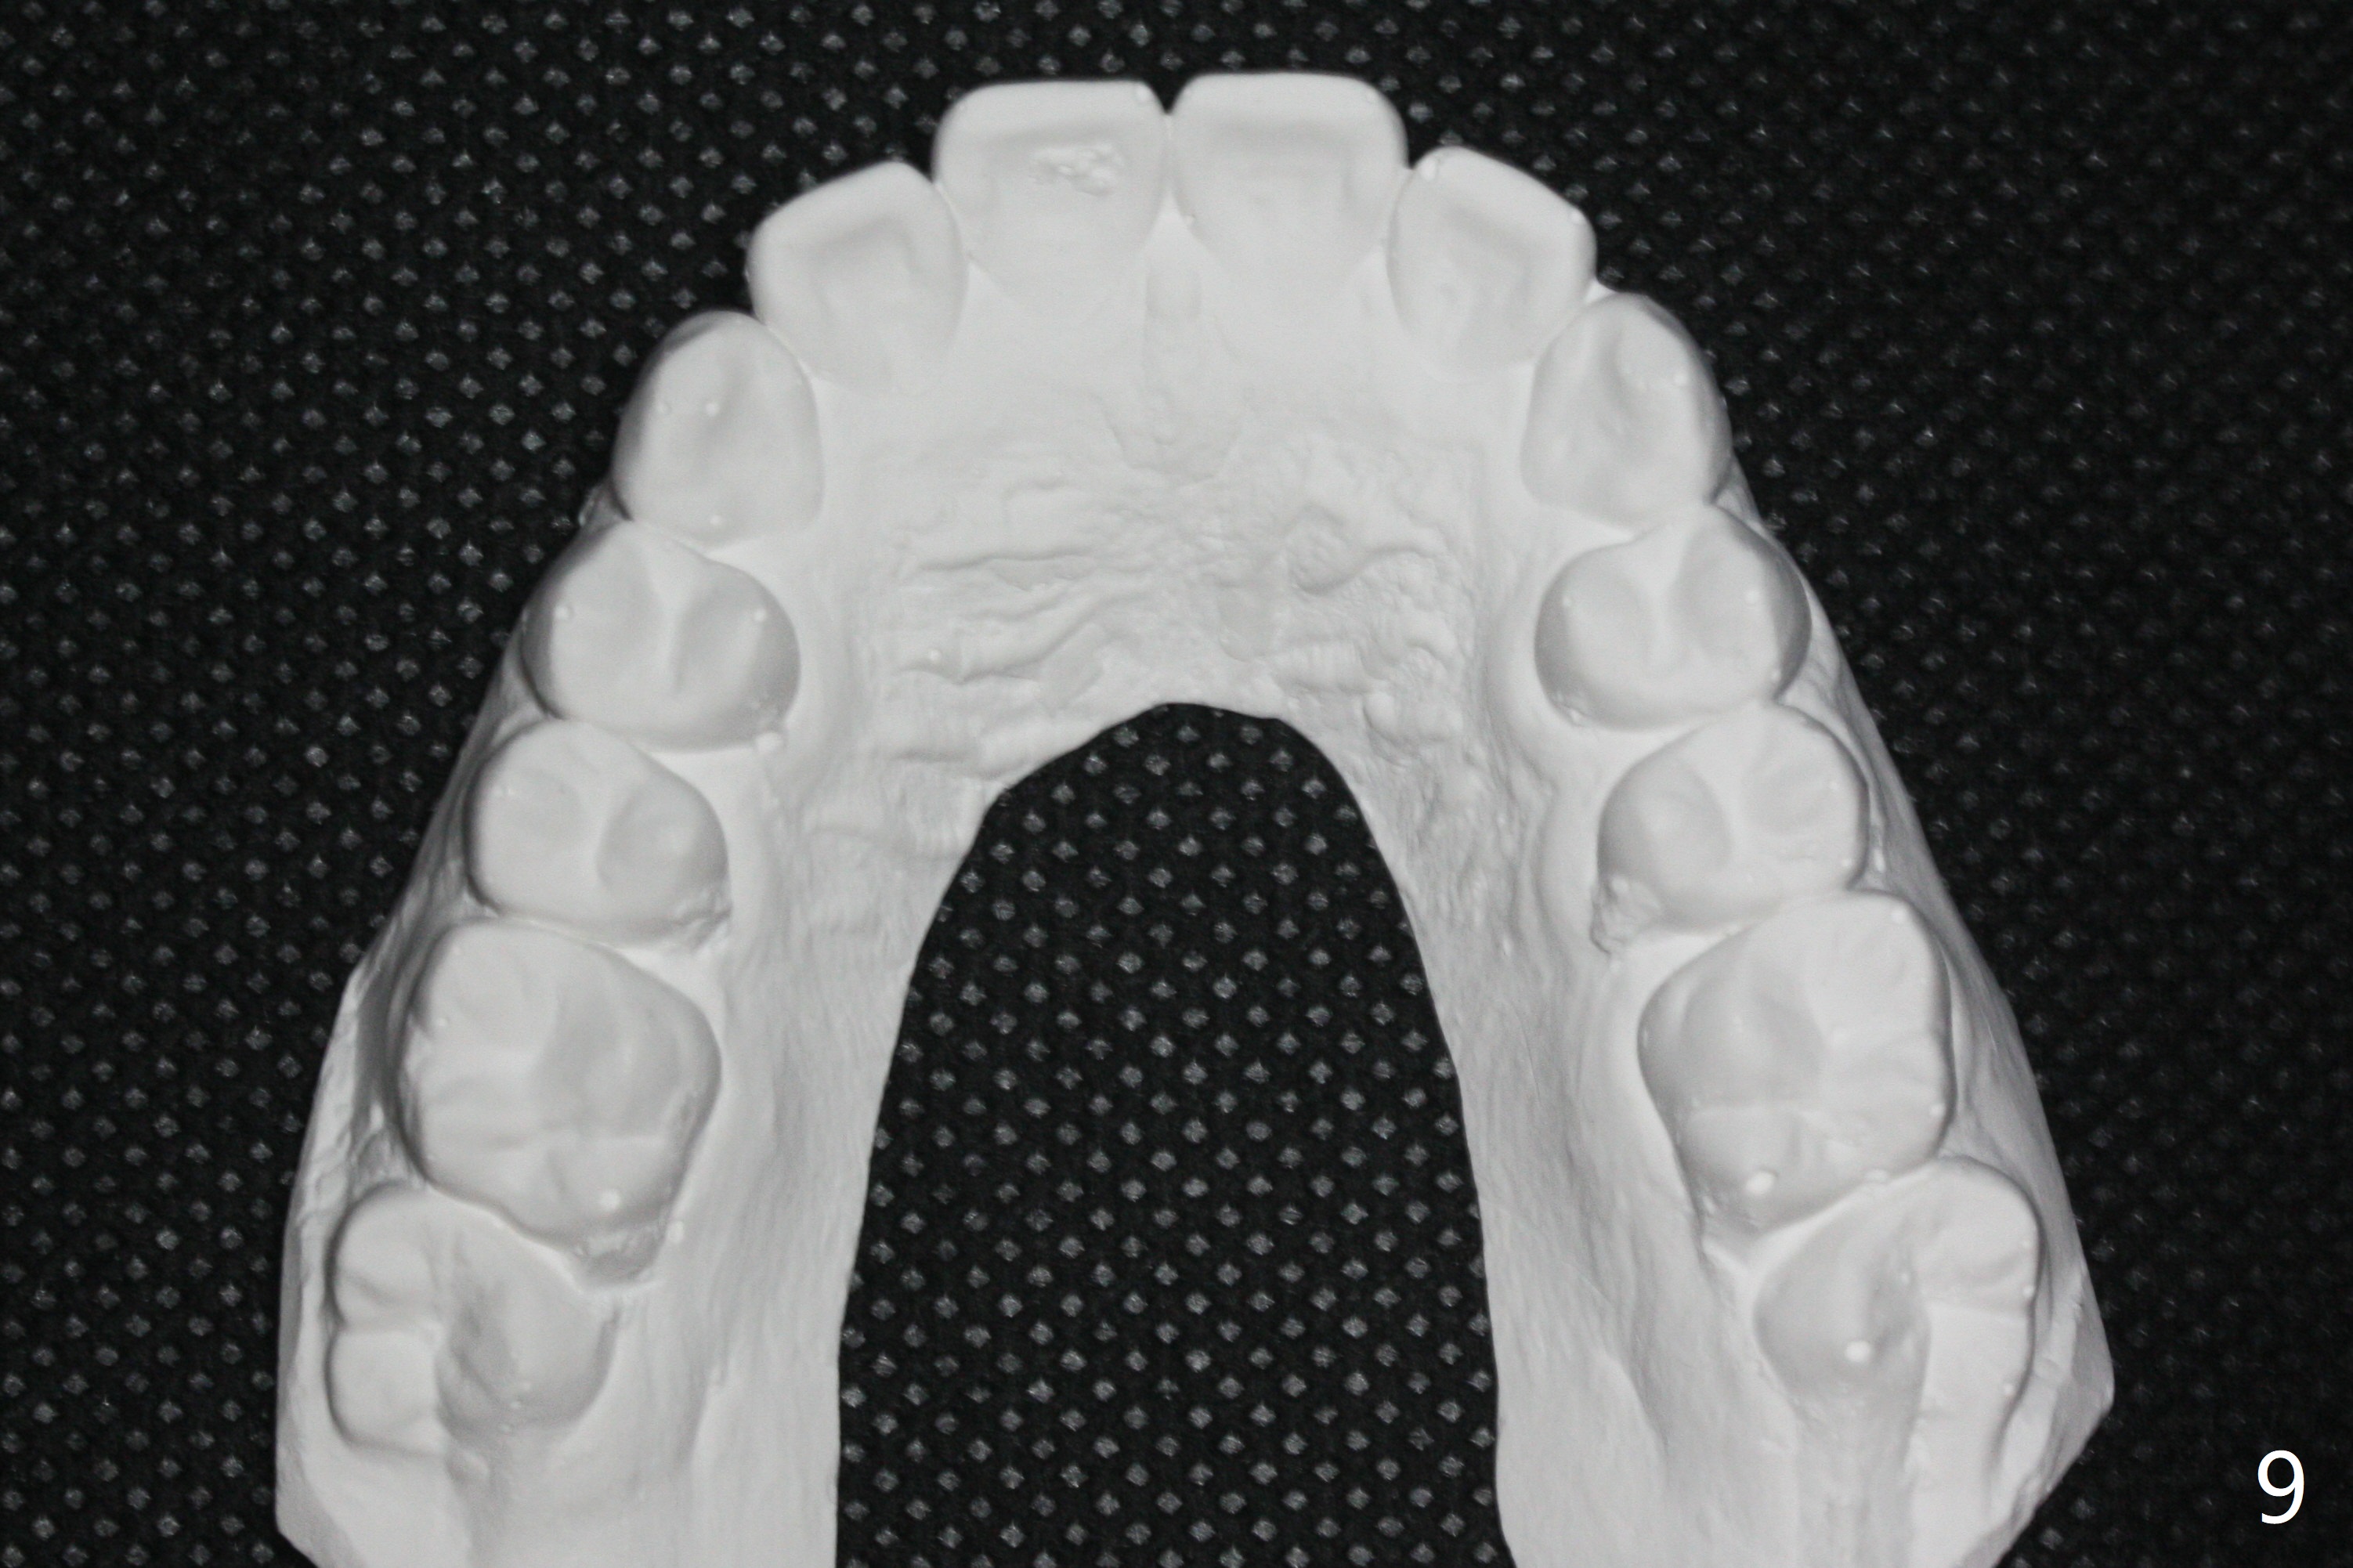

A 11-year-old man starts orthodontic treatment and finishes in 9 months. Two years later crowding relapses because of loss of suck down retainers. It appears that lingual retainer is necessary.